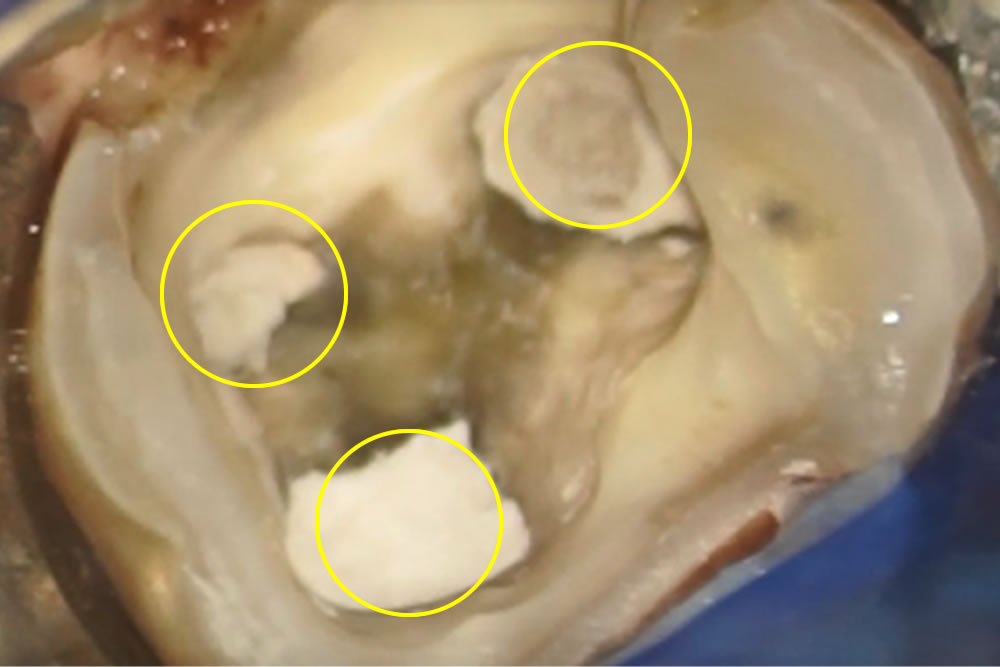

マイクロスコープで視野を拡大して虫歯部分をすべて取った後、根の消毒を始めます。今回の歯は術前にCTで根の入り口が3つあることがわかっています。

根管内の消毒

根管充填

根の中の消毒が終わったら、最終的な薬を詰めて根の中の空洞を封鎖する根管充填(こんかんじゅうてん)を実施。